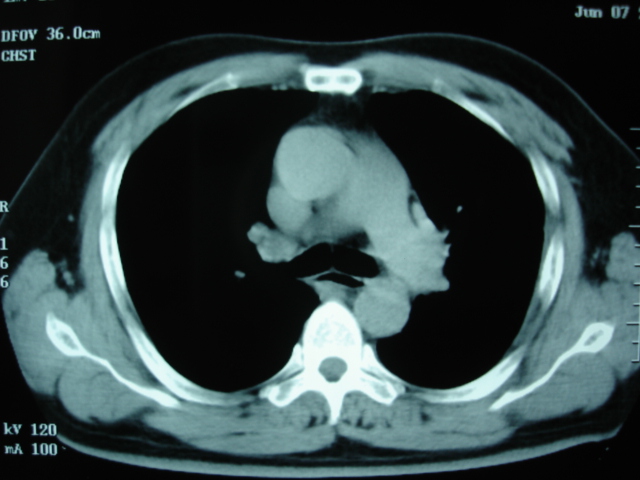

第二次ct2009.6.7 住院后ect未见异常,查痰(阴性)大量抗菌素抗炎一个月后病灶明显变小,7月5号出院后回家后口服抗菌素45天

第三次ct2009.8.21

病灶与胸膜成直边征,考虑炎症假瘤可能性大。

考虑左肺上叶炎症感染(炎性假瘤可能)。

考虑 左肺上叶炎症感染 [炎性假瘤可能性大]。